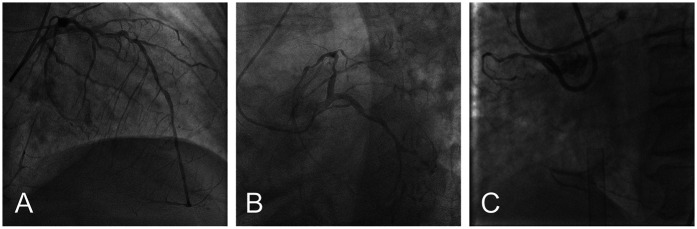

主动脉瓣狭窄(AS)经常与冠状动脉疾病(CAD)相关,特别是在治疗策略缺乏标准化临床指南的高危患者中。我们报告了一例严重AS和高危CAD患者,导致严重的心力衰竭,手术主动脉瓣置换术和冠状动脉搭桥术不适合,因为发病率和死亡率非常高。患者接受了体外膜氧合(ECMO)辅助经导管主动脉瓣置换术(TAVR)和经皮冠状动脉介入治疗(PCI)的一站式手术。术中患者先行预防性静脉-动脉ECMO置管,成功行右冠状动脉和左前降支PCI,然后行TAVR,无并发症。患者对手术的耐受性良好,血流动力学在整个过程中保持稳定。在一年的随访中,患者的心功能明显改善。本病例为治疗高危AS合并CAD提供了宝贵的经验,证明了该方法在临床实践中的可行性和有效性。

Aortic stenosis (AS) is frequently associated with coronary artery disease (CAD), particularly in high-risk patients for whom treatment strategies lack standardized clinical guidelines. We report a case of a patient with severe AS and high-risk CAD, leading to significant heart failure, for whom surgical aortic valve replacement and coronary artery bypass grafting were unsuitable because of very high risk of morbidity and mortality. The patient underwent a one-stop procedure combining extracorporeal membrane oxygenation (ECMO)-assisted transcatheter aortic valve replacement (TAVR) and percutaneous coronary intervention (PCI). During the procedure, the patient first received preventive veno-arterial ECMO placement, successfully underwent PCI on the right coronary artery and left anterior descending artery, and then TAVR was performed without complications. The patient tolerated the procedure well, with hemodynamics remaining stable throughout. At one-year follow-up, the patient's heart function was significantly improved. This case provides valuable experience in treating high-risk AS combined with CAD, demonstrating the feasibility and effectiveness of this approach in clinical practice.